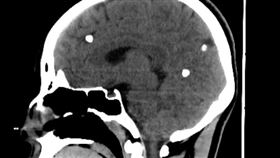

腦囊蟲

愛吃生魚片「寄生蟲入腦」驚人照片曝

福建一名貨車司機蘆先生,3年前因為癲癇反覆發作就醫,...

男頭痛嘔吐 驚見寄生蟲覆蓋大腦神經

中國大陸貴州醫科大學附區醫院日前有一名46歲男病人,...

2018/03/07 11:12